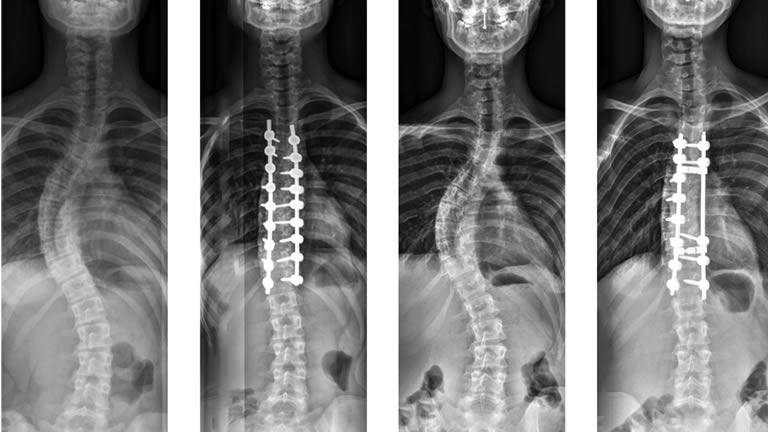

Abnormal curvature of the spine (scoliosis) is repaired. The goal is to straighten the spine to correct the problem in the back.